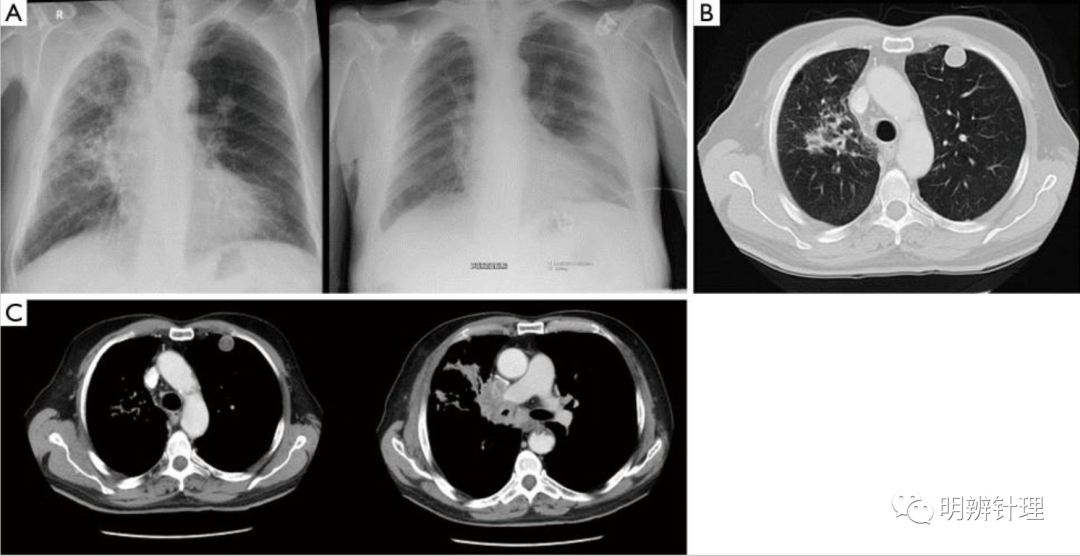

左肺上叶胸膜下圆形结节,边缘光整。右肺上叶近肺门处占位,支气管狭窄。

诊断结果:左肺:错构瘤。 右肺:肺癌。